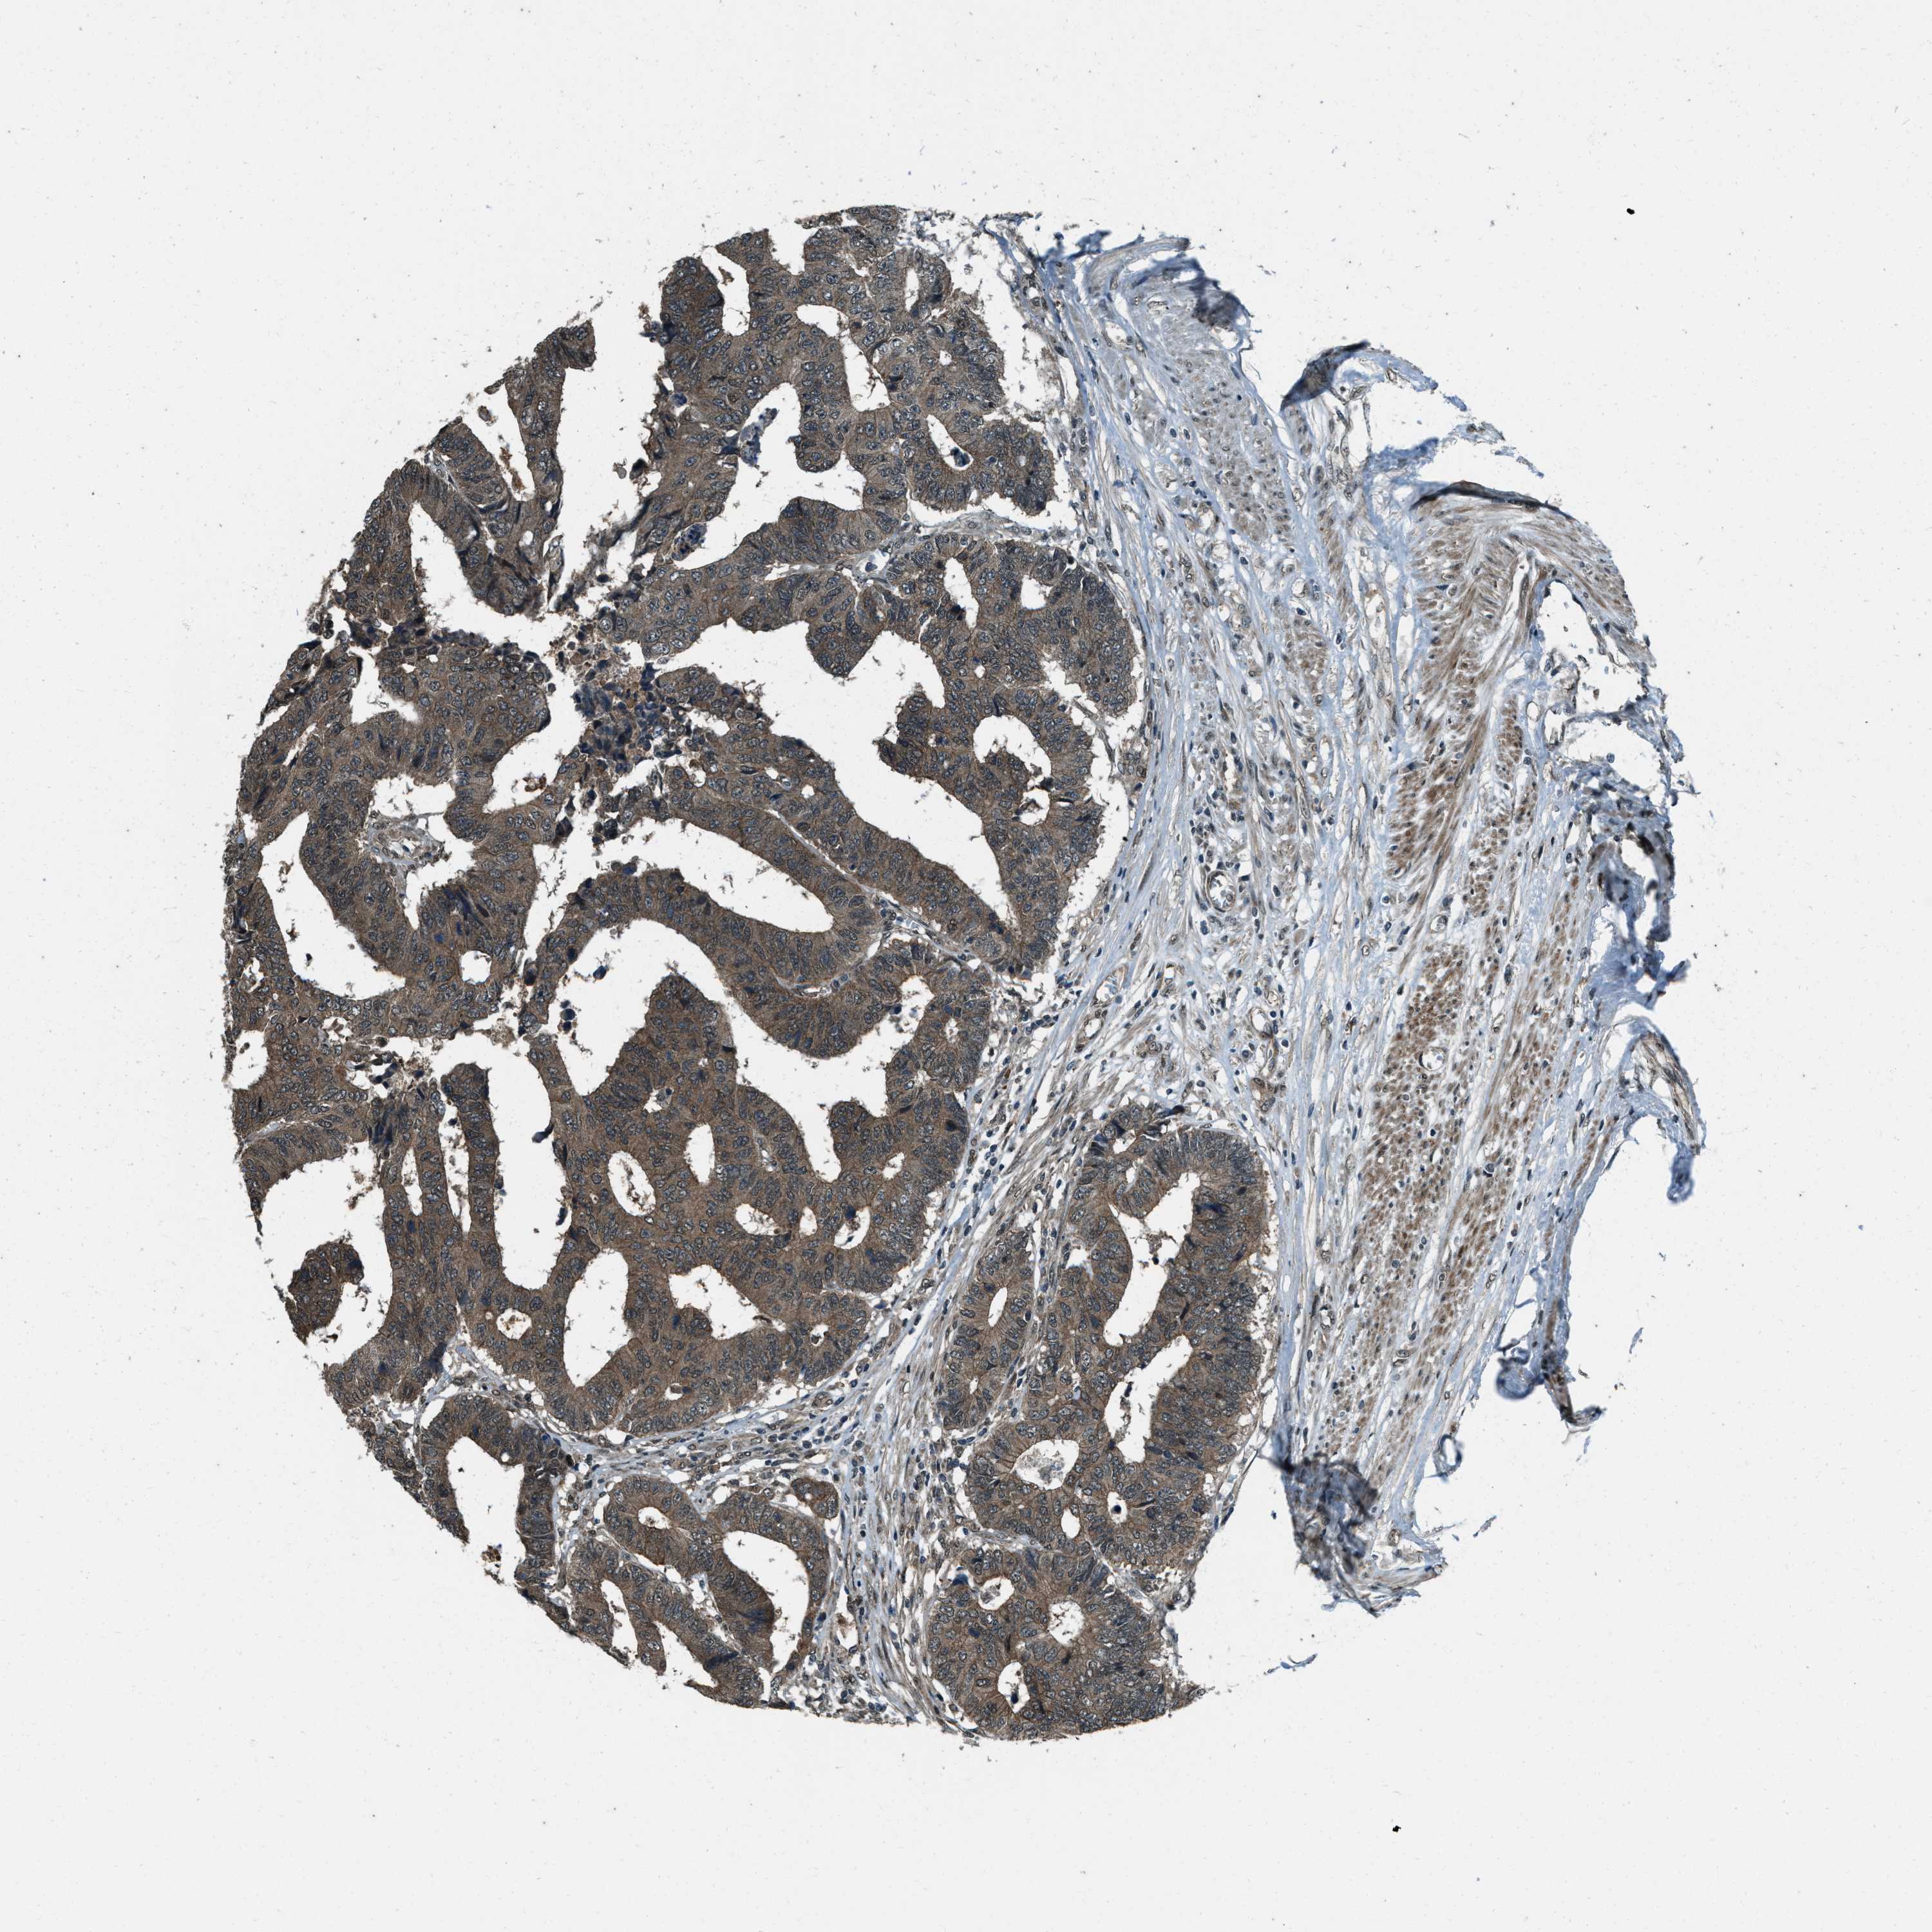

CANCER COLORECTAL CANCER Show tissue menu

COAD TCGA COAD VALIDATION READ TCGA READ VALIDATION PROTEIN COAD CPTAC PROTEIN EXPRESSION

ANTIBODIES

AND

VALIDATION